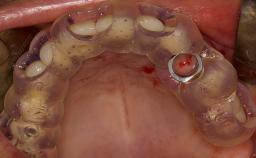

Implant Placement with Simultaneous SFE: Transcrestal Technique with DBBM

Clinical Case Report

Implant Placement with Simultaneous Sinus Floor Elevation (Lateral Window Technique)

Clinical Case Video